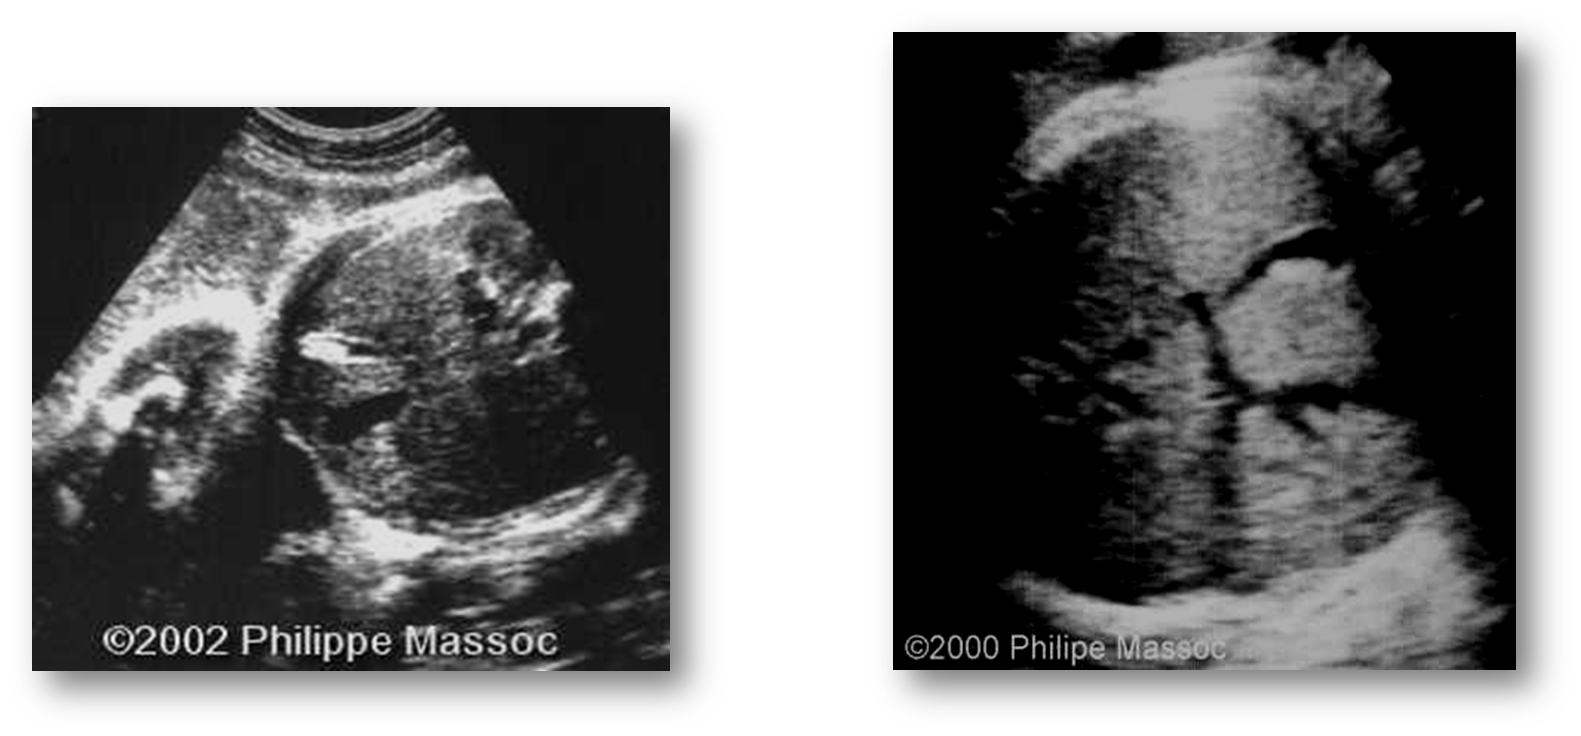

What are these images showing?

Choledochal cyst